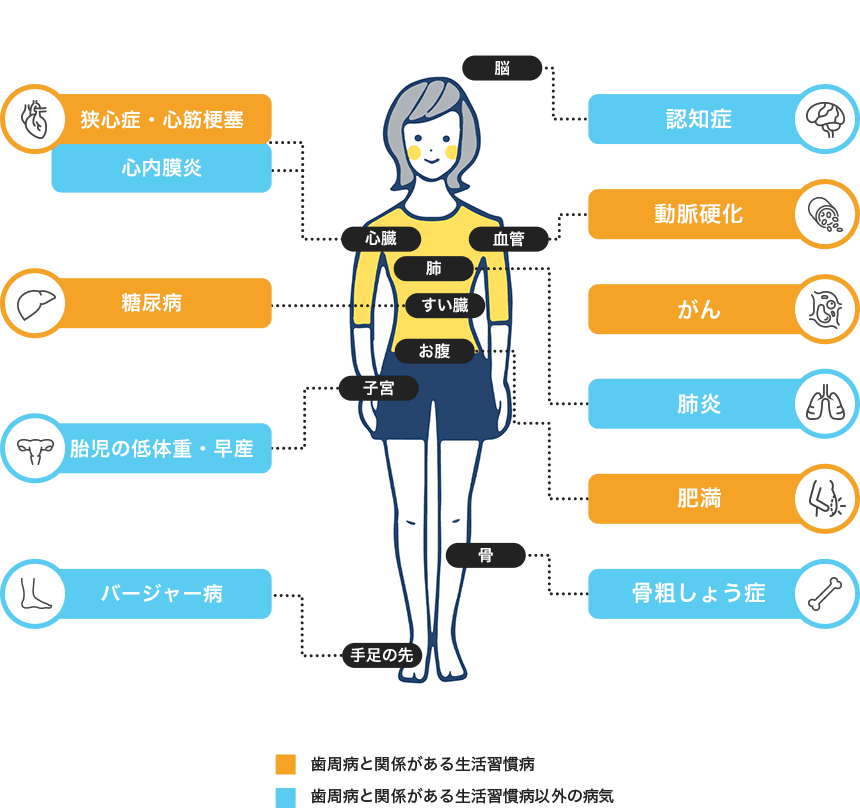

歯周病は、歯を失う一番の原因とされている歯科疾患で、日本では、成人の80%以上が罹患していると言われています。歯周病は虫歯と同様に、最近による感染症です。歯周病は、お口の中で部分的に進行するだけではなく、全身に影響を与える可能性があるのが怖いところなのです。

歯周病菌は、歯と歯茎の間にできる歯周ポケットなどで増殖をしながら、炎症を広げていきます。 そして、この炎症によって作り出された毒素が、歯肉の血管などから入り、体全身をめぐり、様々な病気を引き起こす可能性があるのです。

D i s e a s e 歯周病と全身疾患の関係